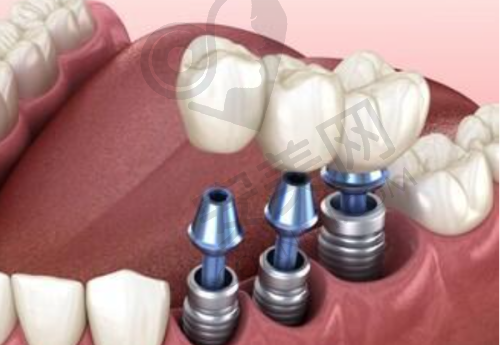

他擅长的项目众多,涵盖了单颗、多颗缺失种植修复、IV即刻负重、即拔即种等。对于各类GBR骨增量手术,他也有着丰富的经验。在面对复杂的口腔情况时,比如骨量不足的患者,他能够熟练运用骨增量技术,为种植牙创造良好的条件。此外,他还擅长常见牙周诊疗、牙列缺损的各类修复以及各种牙体牙髓的治疗等。

周路宽医生在单颗缺失种植修复方面表现出色。单颗牙齿缺失在生活中较为常见,可能会影响患者的咀嚼功能和美观。周路宽医生在处理这类问题时,有着自己独特的方法。

在进行单颗缺失种植修复前,他会对患者的口腔进行全方面的检查,包括牙齿的位置、牙槽骨的情况等。通过详细的检查结果,他能够正确判断患者是否适合种植牙修复。如果患者的牙槽骨条件良好,他会根据患者的牙齿形态、颜色等因素,选择合适的种植体和牙冠。

在种植过程中,周路宽医生操作熟练。他会精细地将种植体植入牙槽骨内,确保种植体的位置和角度符合要求。在牙冠修复阶段,他会注重牙冠与周围牙齿的协调性,使修复后的牙齿在外观上与自然牙齿几乎无差别。

对于患者来说,单颗缺失种植修复后,不仅能够修复正常的咀嚼功能,还能提升面部的美观度。而且,周路宽医生的种植修复成效持久,能够为患者提供长期的口腔健康保护。